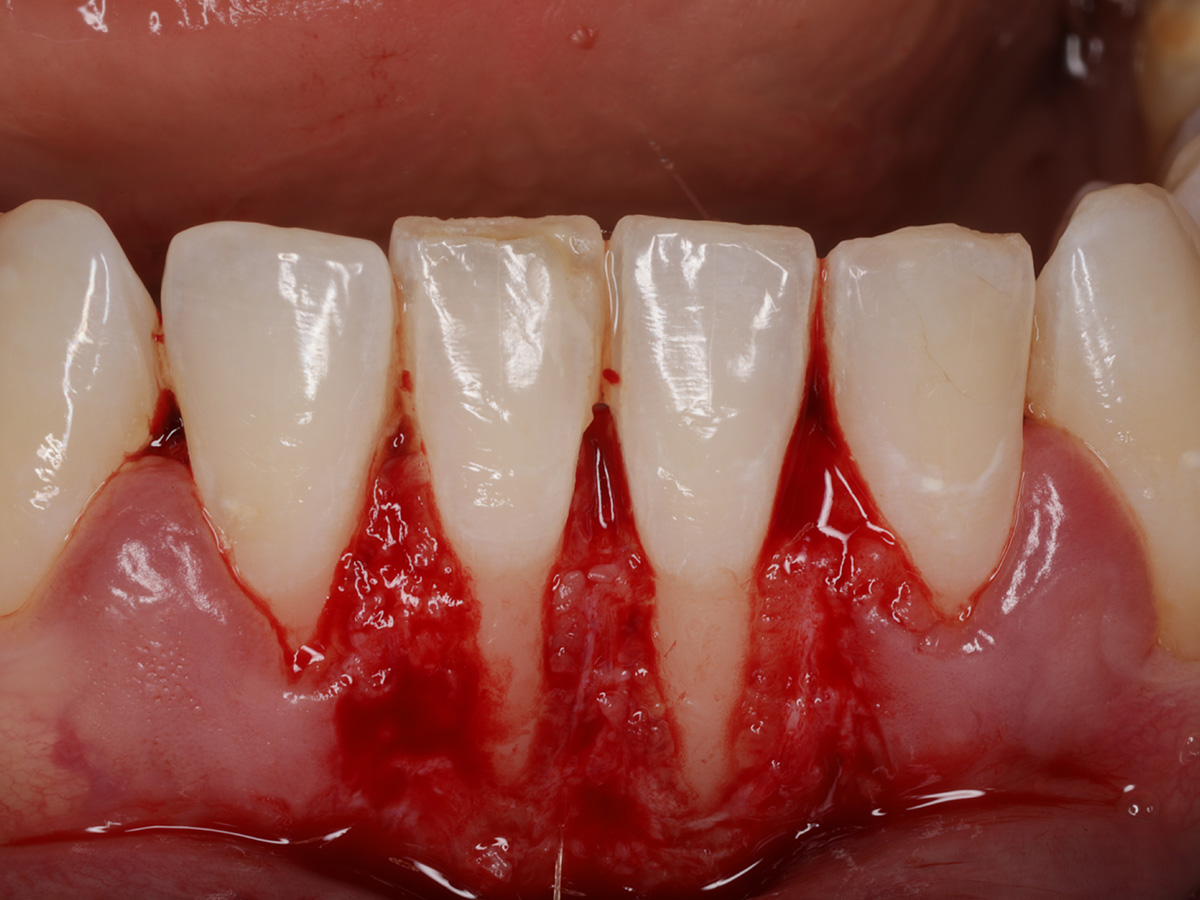

Abbildung 1

Klinische Ausgangssituation mit Rezessionen vom Typ 1 in regio 31/41 und unzureichender Breite und Dicke an keratinisiertem Gewebe.